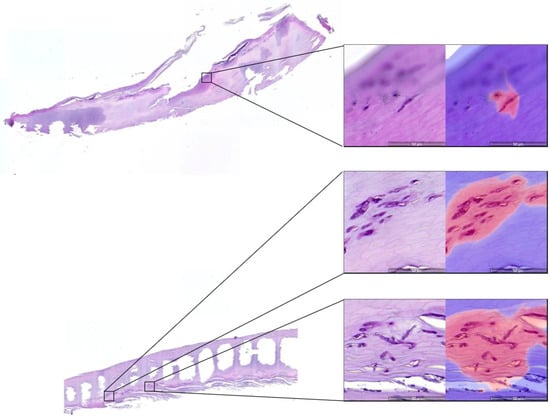

- Decroos, F.; Springenberg, S.; Lang, T.; Papper, M.; Zapf, A.; Metze, D.; Steinkraus, V.; Boer-Auer, A. A Deep Learning Approach for Histopathological Diagnosis of Onychomycosis: Not Inferior to Analogue Diagnosis by Histopathologists. Acta. Derm. Venereol. 2021, 101, adv00532. [Google Scholar] [CrossRef]